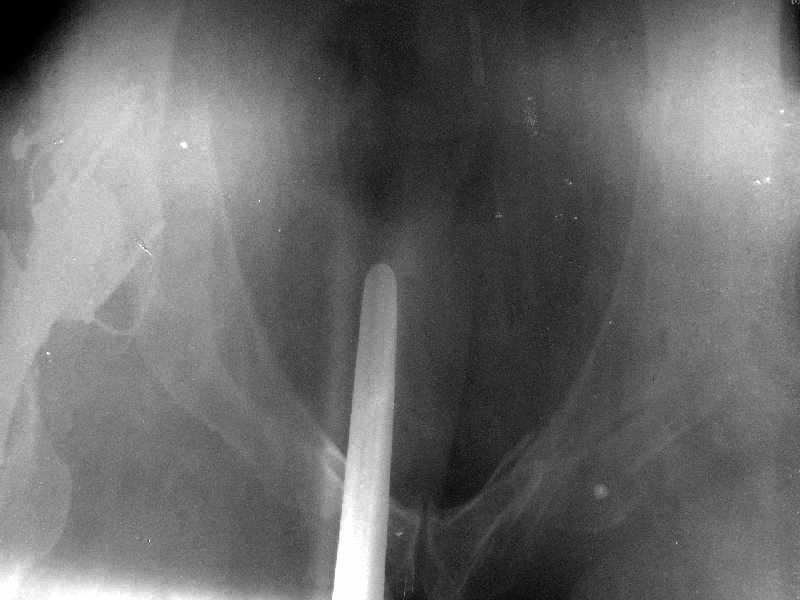

Получила поперечный перелом правой вертлужной впадины (снимок прилагается) с переломом ветвей лонной кости на другой стороне (inlet view также в приложении), а также поперечный перелом дистального метафиза бедра на этой же стороне. Что посоветуете в отношении протеза и впадины? Спасибо заранее.

A colleague of mine from another hospital requests opinion. A female 39 years old was operated ~1 year ago - right side THA for hypoplastic hip. Yesterday she was going to the hospital for THA of the second hip but got involved in a car accident. She admitted with right acetabular and left rami fractures (images attached). Also trasverse fracture of the right distal femur. Seeking your advice regarding the acetabular fracture. THX!